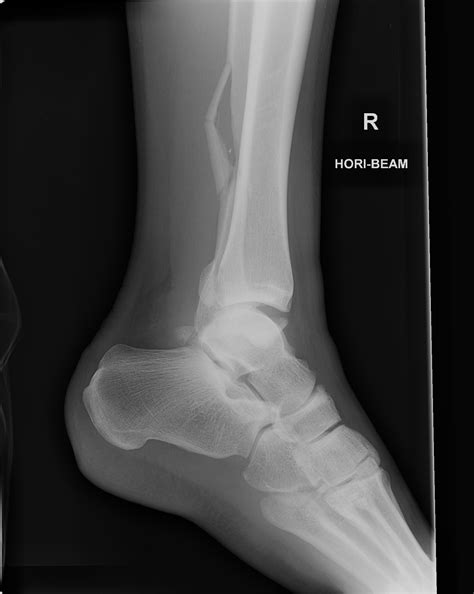

A Normal Ankle Xray is a radiographic image of the ankle joint that shows the bones, joints, and surrounding soft tissues. It is commonly used to diagnose fractures, dislocations, and other abnormalities in the ankle. The procedure is non-invasive and relatively quick, making it a preferred method for initial assessments.

3. Multiple images are taken from different angles to provide a comprehensive view of the ankle joint.

A Normal Ankle Xray typically shows the following structures clearly:

• Tibia and fibula (the two bones of the lower leg)

• Talus (the bone that forms the ankle joint)

• Calcaneus (the heel bone)

• Joint spaces and cartilage

In a normal X-ray, the bones should appear smooth and continuous, with no signs of fractures or dislocations. The joint spaces should be uniform, and there should be no evidence of bone spurs or other abnormalities.

• normal lateral ankle x ray